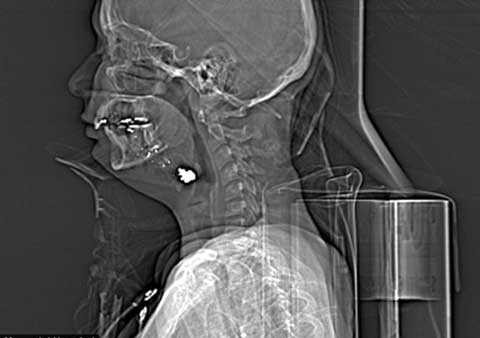

| Viên đạn mắc kẹt trong cổ họng Evenlin |

Ngay sau khi bị bắn, Evenlin đã được đưa tới Bệnh viện Jackson Memorial. Các bác sĩ cho biết đường đi của viên đạn đã khiến rất nhiều bộ phận trên mặt của cô bị thương. Hầu hết các vết thương đều rất nghiêm trọng và nguy hiểm.

Ngày hôm qua Evenlin vừa trải qua một ca phẫu thuật chỉnh hình để thay thế quai hàm bị vỡ bằng một tấm ti tan được trang bị tùy chỉnh.